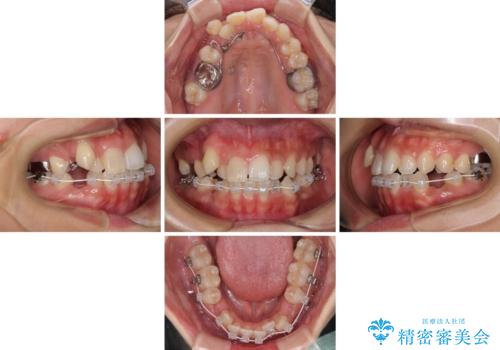

目立たない装置を希望されたので、上顎が裏側装置のハーフリンガルを選択し、上下左右の小臼歯(計4歯)を抜歯して矯正治療を行うこととしました。

補助装置を併用することで、八重歯を速やかに改善し、治療期間の短縮を図ることとしました。

裏側装置での矯正治療は、上顎前歯の正中のズレをまっすぐに改善することが難しいのですが、きれいに整えることができました。

補助装置を用いて抜歯したスペースを速やかに閉じたことで、短期間での治療となりました。